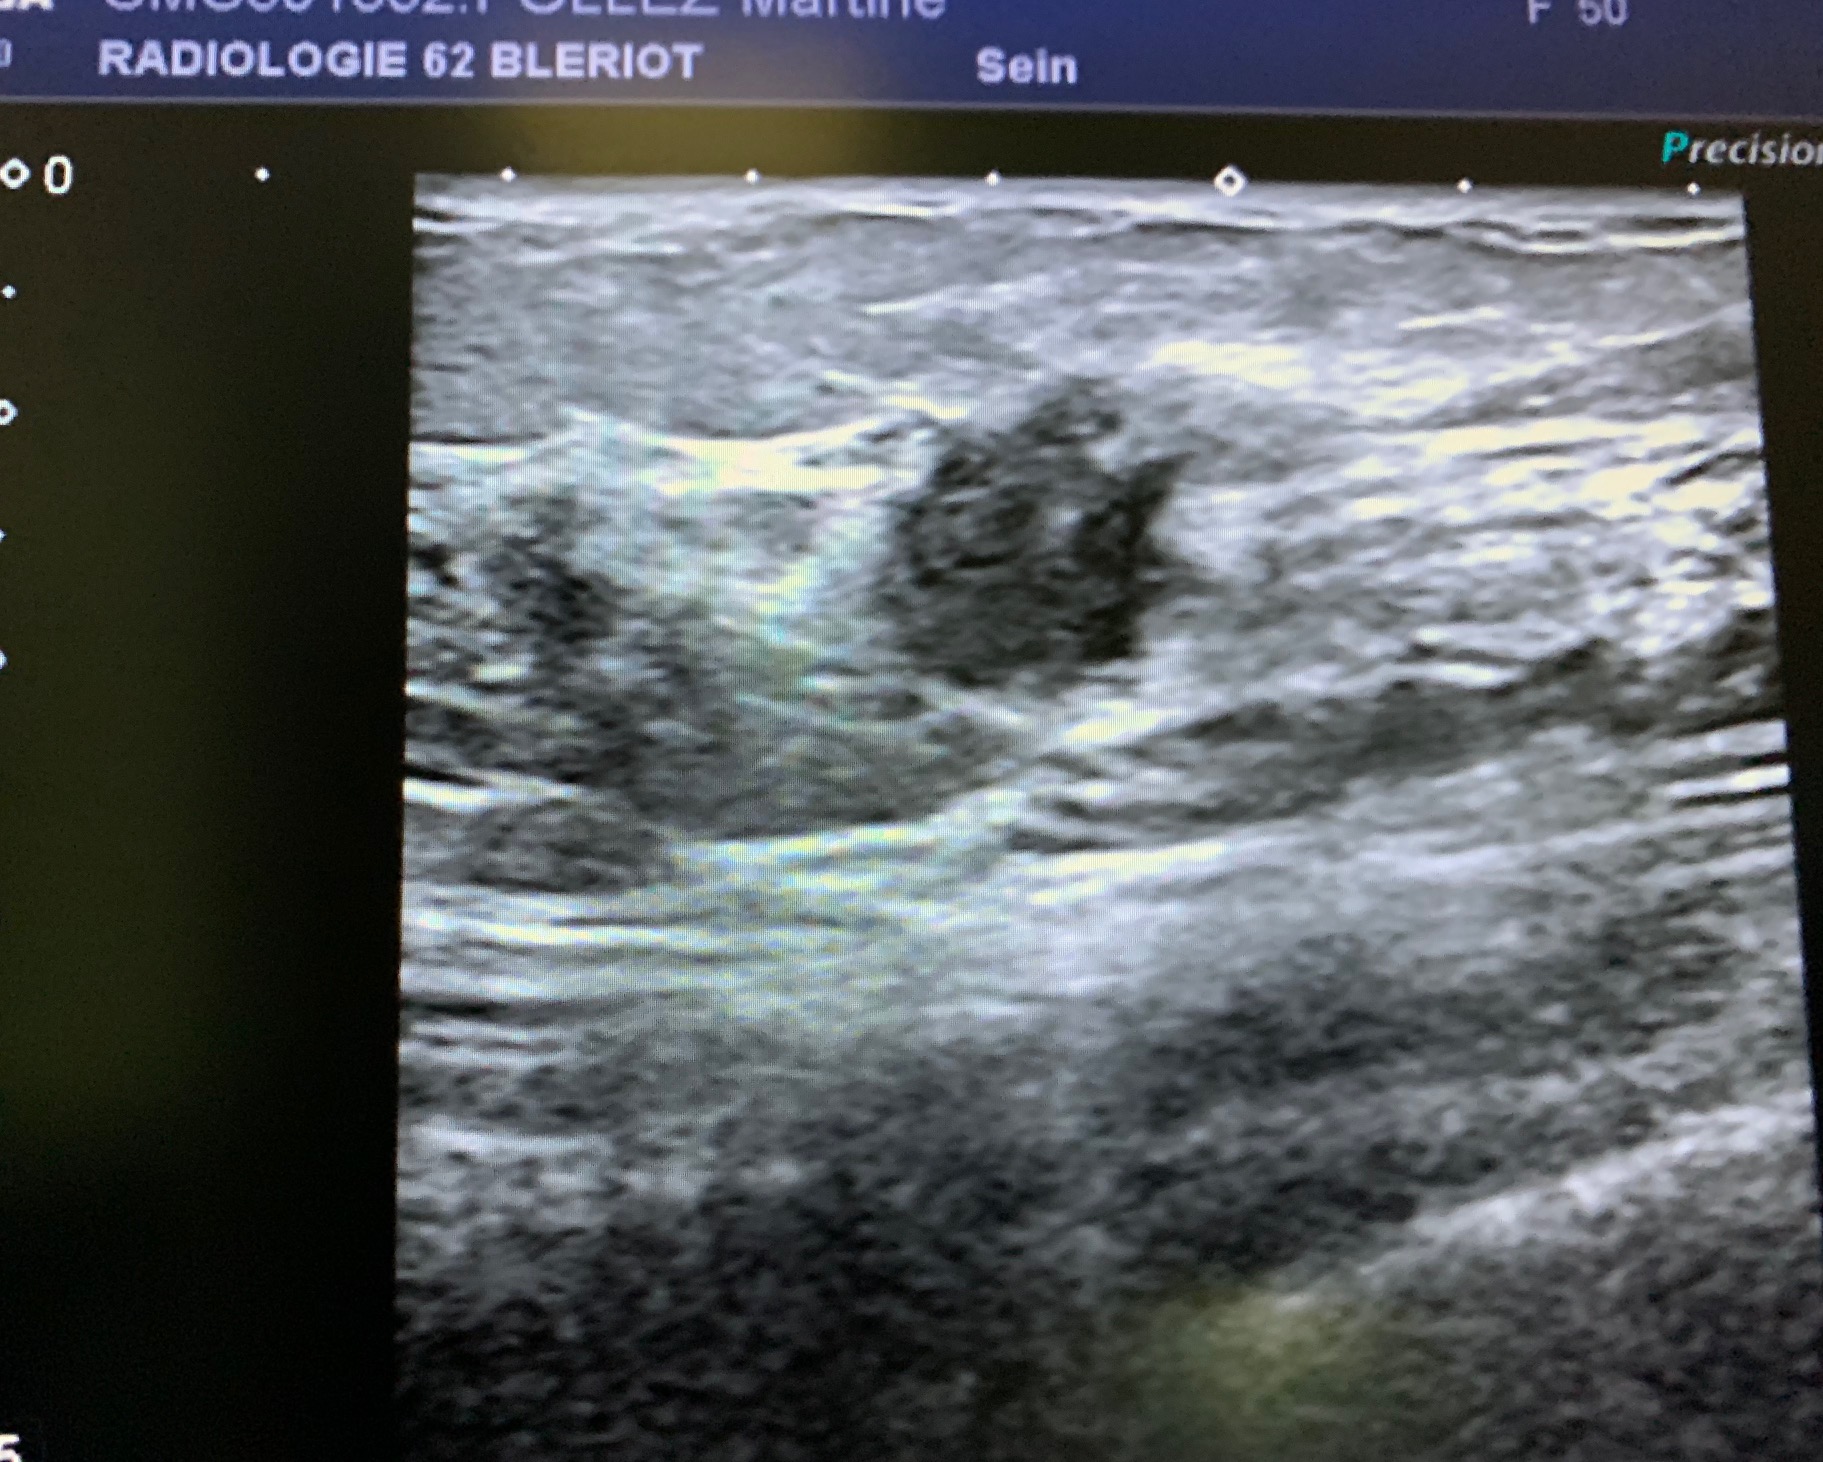

As MammoScreen™ highlighted the case in red, I thought that as a precaution, I should continue. Therefore, I made an ultrasound scan that highlighted a hypoechogenic image with irregular contours, with zones of rigidity under elastographic study, located at the union of the external quadrants of the left breast.

Ultrasound shows a hypoechoic mass with irregular contours and elastographic rigidity.

Breast biopsy: infiltrating carcinoma of luminal HER2+ type.